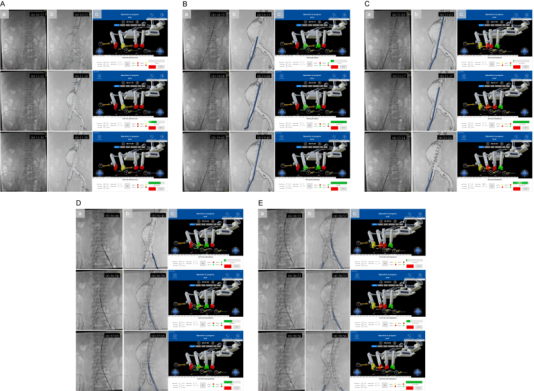

作為國(guó)家“新一代人工智能”專項(xiàng)承擔(dān)單位,奧朋醫(yī)療憑借近百項(xiàng)國(guó)內(nèi)外核心專利技術(shù)儲(chǔ)備,此次手術(shù)實(shí)現(xiàn)四大核心突破,樹立行業(yè)新標(biāo)桿: 01 全球首創(chuàng) EVAR 全流程自動(dòng)化 首次實(shí)現(xiàn)從導(dǎo)絲推進(jìn)、導(dǎo)管輸送到支架精準(zhǔn)釋放的全環(huán)節(jié)無(wú)人干預(yù)操作,徹底突破現(xiàn)有機(jī)器人“手控為主、半自動(dòng)為輔”的技術(shù)局限,將血管介入手術(shù)的自動(dòng)化程度提升至全新高度。 02 獨(dú)創(chuàng)“手術(shù)步驟參數(shù)化”新范式: 基于奧朋醫(yī)療自主研發(fā)的 Endosize軟件,通過(guò)術(shù)前 CTA影像3D重建與精準(zhǔn)建模,將復(fù)雜EVAR手術(shù)拆解為可編程、可重復(fù)的標(biāo)準(zhǔn)單元,自動(dòng)生成器械運(yùn)動(dòng)參數(shù),推動(dòng)血管介入治療從“經(jīng)驗(yàn)依賴”向“標(biāo)準(zhǔn)量化”轉(zhuǎn)型。 03 高兼容+多重安全保障體系: 系統(tǒng)兼容市售主流導(dǎo)絲、導(dǎo)管及支架等常規(guī)耗材,解決了傳統(tǒng)機(jī)器人“耗材適配性差”的行業(yè)痛點(diǎn);內(nèi)置2N力反饋閾值自動(dòng)暫停機(jī)制,搭配人機(jī)協(xié)同檢查點(diǎn)、物理+虛擬雙急停按鈕,實(shí)現(xiàn)“精準(zhǔn)操作+安全可控”的雙重保障。 04 構(gòu)建開(kāi)放式智能介入平臺(tái): 該平臺(tái)依托奧朋醫(yī)療“血管介入領(lǐng)域達(dá)芬奇”的技術(shù)定位,可無(wú)縫拓展至冠脈、神經(jīng)、外周等8大介入領(lǐng)域,為未來(lái)融合AI自主導(dǎo)航、5G遠(yuǎn)程手術(shù)奠定堅(jiān)實(shí)基礎(chǔ),彰顯強(qiáng)大技術(shù)延展性。 圖示:基于3D打印血管模型的體外驗(yàn)證實(shí)驗(yàn)。圖中展示了支架植入的關(guān)鍵步驟,包括主體支架輸送、精確定位、釋放以及分支支架植入。本圖包含三個(gè)視角:(A) 聚焦于血管模型的近景視圖;(B) 展示整個(gè)實(shí)驗(yàn)環(huán)境的廣角視圖;(C) 操作臺(tái)監(jiān)視器界面的截圖。 圖示:自動(dòng)化機(jī)器人輔助EVAR人體驗(yàn)證的支架植入過(guò)程。在導(dǎo)入超硬導(dǎo)絲后(見(jiàn)圖4A),首先以10 mm/s的速度快速將支架輸送系統(tǒng)推進(jìn)至目標(biāo)位置附近,隨后以1 mm/s的慢速進(jìn)行微調(diào),最終實(shí)現(xiàn)支架在目標(biāo)點(diǎn)的精準(zhǔn)定位(見(jiàn)圖4B)。隨后進(jìn)行支架釋放,并通過(guò)逆時(shí)針旋轉(zhuǎn)釋放手柄5400°(轉(zhuǎn)速90°/s)完成裸段釋放過(guò)程(見(jiàn)圖4C)。在人工完成對(duì)側(cè)短腿超選并建立超硬導(dǎo)絲通道后,分支支架以與主體支架相同的方式輸送并釋放(見(jiàn)圖4D、E)。 破解行業(yè)痛點(diǎn),奧朋醫(yī)療給出中國(guó)方案 血管介入手術(shù)機(jī)器人雖已在臨床展現(xiàn)出“提升精度、減少輻射”的顯著優(yōu)勢(shì),但長(zhǎng)期面臨兩大瓶頸:一是難以兼容常規(guī)耗材,無(wú)法滿足EVAR等復(fù)雜多器械協(xié)同手術(shù)需求;二是自動(dòng)化局限于單一步驟,難以實(shí)現(xiàn)全流程閉環(huán)操作。而腹主動(dòng)脈瘤作為“人體定時(shí)炸彈”,其主流治療方式EVAR手術(shù)對(duì)操作精度、流程連貫性要求極高,傳統(tǒng)人工手術(shù)不僅術(shù)者面臨高輻射風(fēng)險(xiǎn),還存在因經(jīng)驗(yàn)差異導(dǎo)致的診療同質(zhì)化難題。 在此背景下,奧朋醫(yī)療深耕“醫(yī)工融合”創(chuàng)新理念,針對(duì)性研發(fā)全自動(dòng)、高兼容、安全可控的主從式血管介入手術(shù)機(jī)器人平臺(tái),精準(zhǔn)破解行業(yè)痛點(diǎn),為復(fù)雜血管介入手術(shù)提供了兼具臨床適配性與技術(shù)先進(jìn)性的中國(guó)解決方案。 硬核技術(shù)支撐,臨床數(shù)據(jù)彰顯實(shí)力 該平臺(tái)依托奧朋醫(yī)療“血管介入領(lǐng)域達(dá)芬奇”的技術(shù)定位,可無(wú)縫拓展至冠脈、神經(jīng)、外周等8大介入領(lǐng)域,為未來(lái)融合AI自主導(dǎo)航、5G遠(yuǎn)程手術(shù)奠定堅(jiān)實(shí)基礎(chǔ),彰顯強(qiáng)大技術(shù)延展性。 本次研究采用奧朋醫(yī)療自主研發(fā)的主從式機(jī)器人平臺(tái),集成多自由度機(jī)械臂與高精度驅(qū)動(dòng)模塊,通過(guò)“術(shù)前精準(zhǔn)規(guī)劃—術(shù)中自動(dòng)執(zhí)行—階段協(xié)同確認(rèn)”的閉環(huán)流程,實(shí)現(xiàn)毫米級(jí)操作精度。研究先經(jīng)3D打印血管模型充分驗(yàn)證,再成功應(yīng)用于4例腎下型腹主動(dòng)脈瘤患者,取得卓越臨床成果: ? 手術(shù)成功率100%:4例患者均順利完成全流程自動(dòng)化手術(shù),術(shù)后CTA證實(shí)支架定位精準(zhǔn),無(wú)內(nèi)漏及相關(guān)并發(fā)癥; ? 診療效率大幅提升:平均手術(shù)時(shí)間僅110分鐘,透視時(shí)間19分鐘,較傳統(tǒng)手術(shù)顯著縮短; ? 輻射防護(hù)成效顯著:術(shù)者輻射劑量低至4mGy,較傳統(tǒng)手術(shù)減少90%以上,從根本上保障醫(yī)護(hù)人員職業(yè)健康; ? 穩(wěn)定性全面驗(yàn)證:所有自動(dòng)化步驟均未發(fā)生意外中斷,無(wú)需人工接管,充分證明系統(tǒng)的臨床可靠性。 (圖示:血管介入手術(shù)機(jī)器人的組成與工作原理。(A) 血管介入手術(shù)機(jī)器人整體示意圖。手術(shù)過(guò)程中,術(shù)者坐于操作臺(tái)前(位于鉛屏后方),遠(yuǎn)程控制從端機(jī)械單元;(B) 操作臺(tái)的顯示界面與功能說(shuō)明;(C) 自動(dòng)化機(jī)器人輔助EVAR手術(shù)的執(zhí)行流程圖。) (圖示:基于Endosize軟件的EVAR術(shù)前規(guī)劃。圖中展示了中心線及關(guān)鍵定位點(diǎn)。導(dǎo)絲的移動(dòng)距離為從Pl點(diǎn)至P1點(diǎn);導(dǎo)管的移動(dòng)距離為從Pr點(diǎn)至P2點(diǎn);主體支架的移動(dòng)距離為從Pr點(diǎn)至P3a點(diǎn);分支支架的移動(dòng)距離為從Pl點(diǎn)至P4a點(diǎn)。) 引領(lǐng)行業(yè)變革,繪就智能介入新藍(lán)圖 作為當(dāng)前全球唯一實(shí)現(xiàn)冠脈、外周、主動(dòng)脈介入手術(shù)同步臨床推進(jìn)的企業(yè),奧朋醫(yī)療此次突破性成果,不僅驗(yàn)證了全自動(dòng)化EVAR手術(shù)的臨床可行性,更通過(guò)標(biāo)準(zhǔn)化范式構(gòu)建,為縮小不同層級(jí)醫(yī)療機(jī)構(gòu)技術(shù)差距、提升基層診療同質(zhì)化水平提供了有效路徑。 未來(lái),奧朋醫(yī)療將持續(xù)深化“精準(zhǔn)、智能、微創(chuàng)”的技術(shù)理念,進(jìn)一步拓展該平臺(tái)至復(fù)雜主動(dòng)脈病變、神經(jīng)血管介入等更多場(chǎng)景,并融合AI實(shí)時(shí)導(dǎo)航、5G遠(yuǎn)程手術(shù)等前沿技術(shù),推動(dòng)血管介入手術(shù)向“自主決策、全域覆蓋、優(yōu)質(zhì)資源下沉”的更高階段邁進(jìn)。正如奧朋醫(yī)療的發(fā)展愿景——致力于成為“血管介入領(lǐng)域的達(dá)芬奇”,以中國(guó)智造打破國(guó)際技術(shù)壟斷,為全球患者帶來(lái)更安全、更高效、更可及的醫(yī)療服務(wù)。